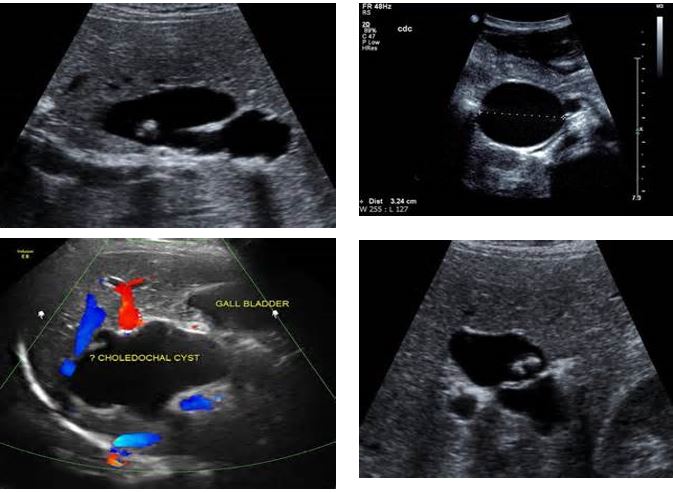

4 pics of Choledochal Cysts

Type I is a fusiform dilation of the common bile duct is Most common, along with type Iva

Choledochal Cysts